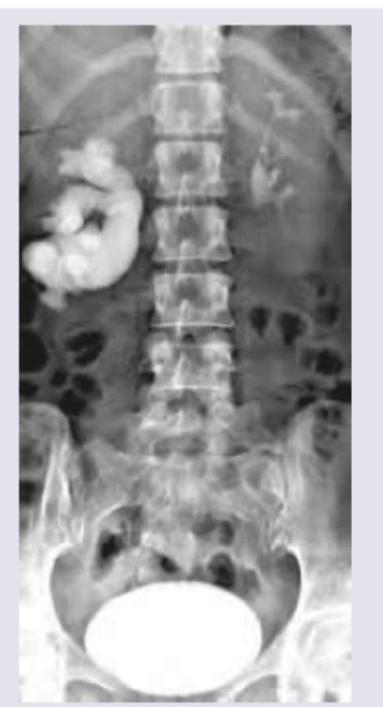

Question 24: The given IVU shows:

- A. Hydronephrosis

- B. Horseshoe kidney (Correct Answer)

- C. Polycystic kidney

- D. Duplication of collecting system

Explanation: ***Horse shoe kidney*** - The IVU image clearly shows both kidneys are **fused at their lower poles**, forming a 'U' shape across the midline, characteristic of a **horseshoe kidney**. - This fusion often results in the kidneys lying lower in the abdomen and can cause anatomical variations in the **collecting system and vasculature**, as hinted by the lower position and altered calyces. *Hydronephrosis* - **Hydronephrosis** would manifest as **dilatation of the renal pelvis and calyces** due to urine outflow obstruction. - While horseshoe kidneys can be prone to hydronephrosis due to their abnormal anatomy, the primary finding here is the fusion, not significant dilatation. *Polycystic kidney* - **Polycystic kidney disease** would present with multiple **cysts replacing normal kidney parenchyma**, leading to enlarged, typically non-functioning kidneys. - The image does not show multiple fluid-filled sacs or significant renal enlargement typical of polycystic disease. *Duplication of collecting system* - A **duplication of the collecting system** (e.g., duplicate ureters) would show two distinct collecting systems draining from a single kidney. - The image shows a single collecting system for each kidney, albeit abnormally shaped due to the fusion, but not duplicated.